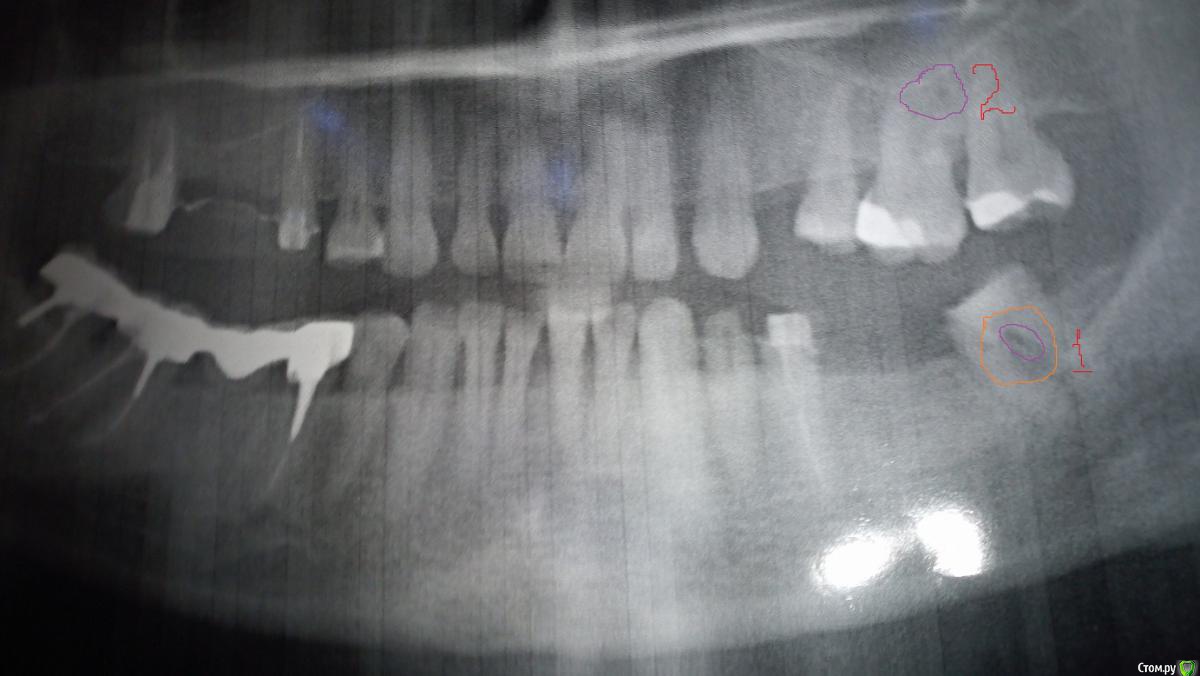

пациент Елена Опубликовано 29 декабря, 2018 Поделиться Опубликовано 29 декабря, 2018 (изменено) Уважаемые доктора, здравствуйте! Если возможно, помогите, пожалуйста, советом. Моей маме 57 лет, в этом году занялась зубами ( изначально диагностировали кисту в гайморовой пазухе справа, в связи с этим пошла на диагностику состояния 17, 15 зубов, 16 удален. Ну и в процессе этого выявилось, что надо лечить почти все). И в общем ситуация возникла такая- на 37 и 35 зубе находился мост, 36 отсутствует. 35 зуб полечили и поставили штифт, 37 врач открыл и пошел в медиальный канал. Пройти не смог, сказал что зуб резорциненный. При этом насколько я поняла по снимку допустил небольшую перфорацию. Сразу зуб закрыл временной пломбой, сказал что однозначно под удаление и имплант. Мама пошла к другому врачу, полечили дистальный канал, его прошли спокойно, сейчас там заложена паста для лечения периодонтита. На снимке КТ видно образование в области медиального канала и между корнями, врач сказал киста. Мама связалась с еще одним доктором ( у которого есть микроскоп), та сказала, что это не киста, а гранулема, сказала, что попробует пройти каналы под микроскопом. Я почитала информацию по этой проблематике и сделала вывод, что раз тот врач, который уже попробовал пройти, не смог и перфорировал, вряд ли это получится и под микроскопом. Верно ли я думаю? Прикрепляю снимки- первый снимок это КТ до попытки лечения, на ней видно эти гранулемы. Второй снимок- это ОПТГ после лечения. Если возможно, помогите пожалуйста с моими вопросами:1)перфорирован ли все таки зуб? я отметила это на снимке цифрой 1 ( на ортопантомограмме после попытки входа в канал)2)Цифрой 2 отметила какое то затемнение на 26 зубе, это тоже подобное образование?3) стоит ли пытаться проходить каналы под микроскопом или лучше не лезть и думать уже над вопросом 4----4) если не полечить- удалять или все таки учитывая небольшой размер и отсутствие клинических проявлений в принципе посидеть на "пороховой бочке", прикрыть это всё недорогим мостом?5) и последний вопрос- нужно ли как то закрывать перфорацию ( если это перфорация)? может быть, как раз это и сделать под микроскопом? Заранее огромное спасибо!! Изменено 29 декабря, 2018 пользователем пациент Елена Ссылка на комментарий